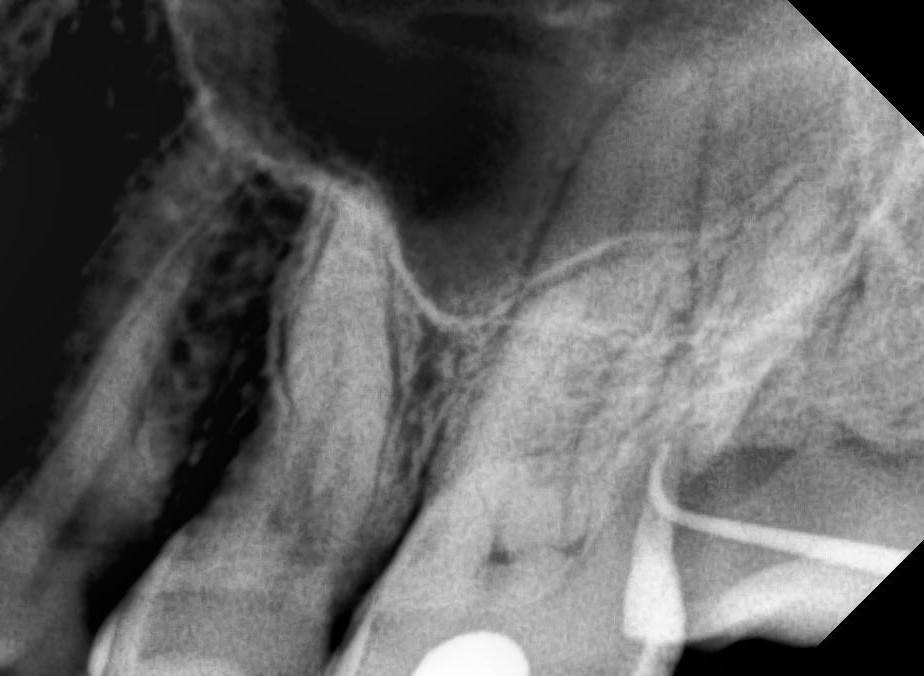

Kolchanov Опубликовано 19 августа, 2023 Поделиться Опубликовано 19 августа, 2023 Есть вот такой зуб 26. На дистальном корне рецессия, парадонтальный карман и дефект на корне явно не кариозного происхождения. Может кто покрутить КТ и сказать свои мысли по поводу процесса. https://drive.google.com/drive/folders/1B2huzkpPolt4XsAAIdYJuWwHHcJvr7iK?usp=drive_link Меня смущает, что, похоже, и на 28 (27 удалён) есть изменения и костная ткань тоже выглядит как-то подозрительно. Ссылка на комментарий

Kolchanov Опубликовано 22 августа, 2023 Автор Поделиться Опубликовано 22 августа, 2023 Симптоматики как таковой нет. Холодовая секунд пять. При перкуссии не боль, но неприятно. По анамнезу, говорит, что болел когда-то. Ссылка на комментарий

Carioznik Опубликовано 22 августа, 2023 Поделиться Опубликовано 22 августа, 2023 Кажется, как будто, пациент что-то там в этой область делал нехорошее, может вредная привычка какая? Ортодонтия там раньше была? Старые КТ-шки есть? Ссылка на комментарий